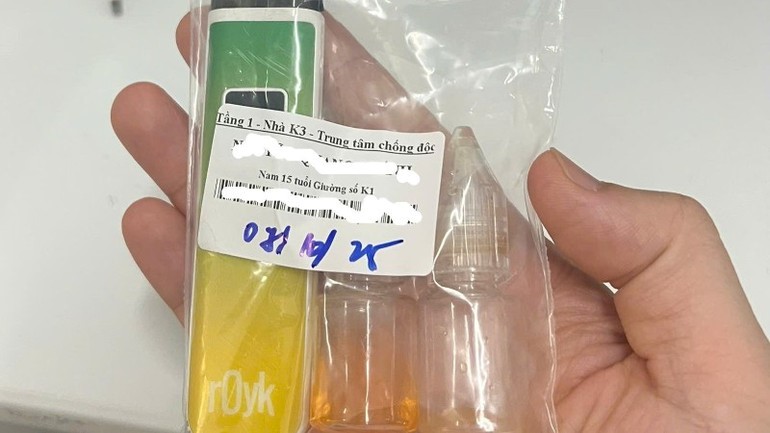

Rất nhiều chất độc có trong thuốc lá điện tử

Sunday 2025-11-16 08:35Do nguy cơ cao ảnh hưởng với sức khỏe con người và tính chất đa dạng, phức tạp không thể kiểm soát, chính phủ nhiều nước đã đưa ra các quy định quản lý hoặc cấm hoàn toàn các hương liệu...

Quảng Trị: Kịp thời cứu cháu bé bị kim chọc tủy rơi vào đường thở

Sunday 2025-11-16 08:23Ngày 15/11, Bệnh viện Đa khoa tỉnh Quảng Trị cho biết vừa cấp cứu thành công một cháu bé 3 tuổi bị kim chọc tủy dài 22mm rơi vào đường thở. Dị vật trong đường thở của bệnh...